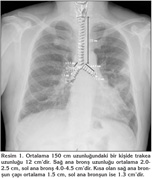

Trakea servikal 6-7. vertebralarla torakal 4-5. vertebralar aras?nda yer al?r.? Ekstratorasik (servikal) ve intratorasik par?alar? vard?r. Suprasternal ?entikten karinaya kadar uzanan intratorasik par?a ki?inin boyun yap?s?na g?re yakla??k 6-8 cm kadard?r. Trakean?n ?ap? kad?nlarda erkeklere oranla daha azd?r. Trakean?n rijiditesinden ?n ve yanlar? olu?turan ve say?lar? 18-24 aras?nda de?i?en C ?eklinde k?k?rdak yap?lar sorumludur. Eri?kinlerde ortalama 2 adet/cm ?eklindedir. Posterior duvar ise ince adele ve membranlardan olu?ur. K?k?rdak halkalardan olu?an rijid duvar?n anteriorda, membran?z duvar?n posteriorda olmas? bronkoskopiyi yapan ki?inin oryantasyonu i?in ?nemlidir. B?ylelikle sa? ve sol ana bron?lar tan?n?r. Krikoid k?k?rdak, karina seviyesi ve posterior membran?z duvar?n tan?nmas? lokalizasyon ve oryantasyon i?in ?ok ?nemlidir (Resim 1).

Karina arkada torakal 4-5. vertebra, ?nde angulus sterni seviyesindedir. Olu?turdu?u a?? 55-70 derecedir. Sa? ana bron? trakea orta hattan ortalama 25, sol ana bron? ise 45 derece a?? ile ayr?l?r,? soldan daha k?sa ve daha geni?tir. Sa? ana bron? bitiminde lateralden sa? ?st lob orijin al?r.